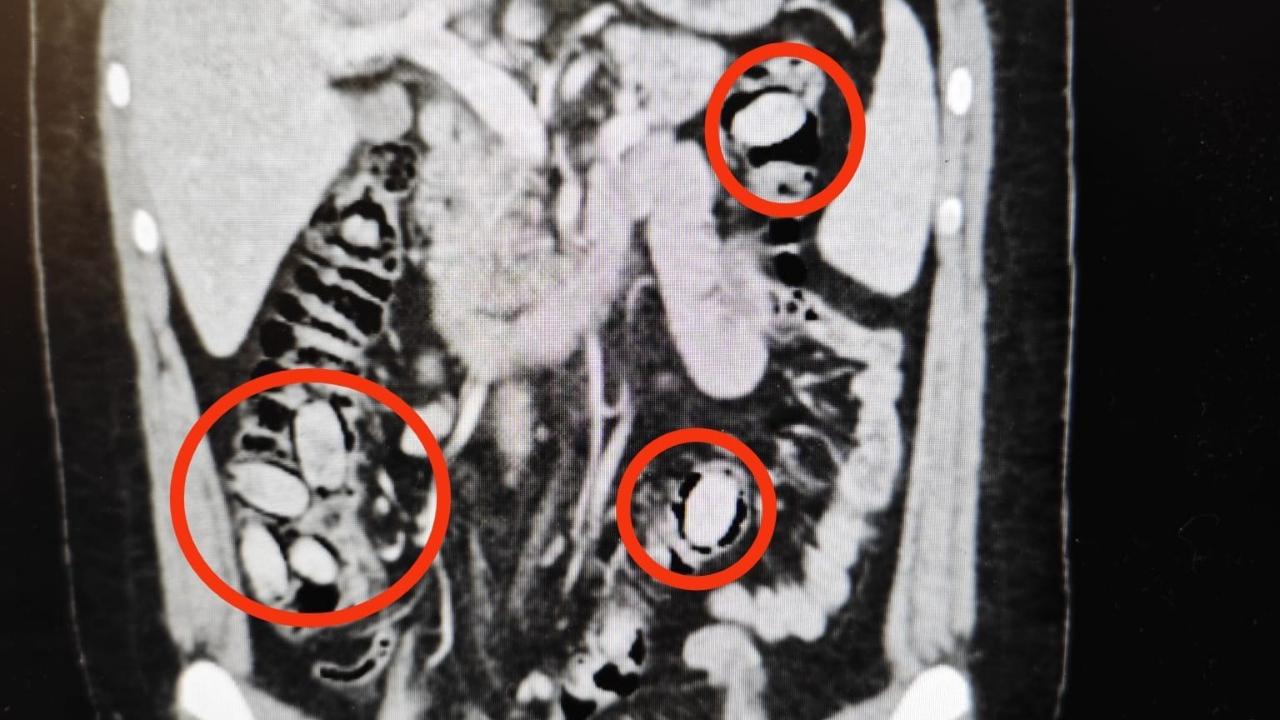

Edinilen bilgilere göre, S.A. (25) isimli yabancı uyruklu şahıs, Eskişehir girişinde bulunan uygulama noktasında polis ekiplerinin şüpheli davranışları fark etmesi üzerine durduruldu. Şahsın sağlık durumundan kuşkulanılması üzerine hastaneye sevk edildiği öğrenildi. Burada yapılan detaylı tetkikler sonucunda, S.A.’nın yutmak suretiyle midesinde 44 kapsül metamfetamin taşıdığı tespit edildi.

Doktorlar tarafından gerçekleştirilen cerrahi operasyonla uyuşturucu maddeler güvenli şekilde şahsın midesinden çıkarıldı. Tedavisinin tamamlanmasının ardından emniyetteki işlemleri tamamlanan S.A., sevk edildiği adli makamlarca tutuklanarak cezaevine gönderildi.